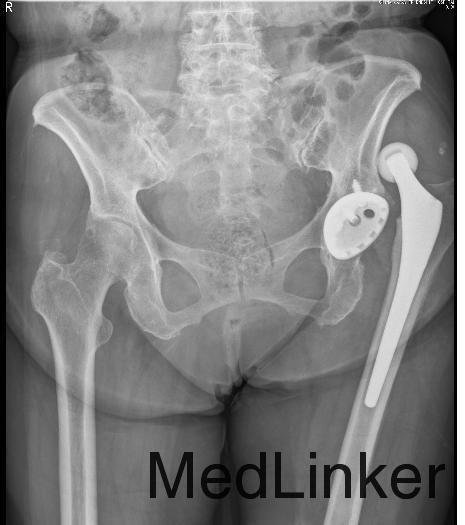

患者女,86岁,主因“左髋部疼痛3小时”收入院。患者于3小时前起床,起初端坐于床边,转动身体后出现左髋部疼痛、畸形,以左臀部、左大腿外侧明显,疼痛可以忍受,左髋关节无法伸直,后就诊于我院急诊行X线检查诊断为左髋关节脱位,患者1月前因股骨颈骨折于外院行全髋关节置换术,现为求进一步治疗,来我院就诊并收住入院。

查体:平车推入病房,急性病容,左髋保持屈曲位,内收内旋缩短畸形。双下肢足背动脉搏动良好,左股四头肌肌力Ⅲ级。 辅助检查:X线:髋关节正位:左侧人工髋关节置换术后并假体脱位。

诊断:左髋置换术后髋关节脱位; 治疗:急诊行髋关节复位术。